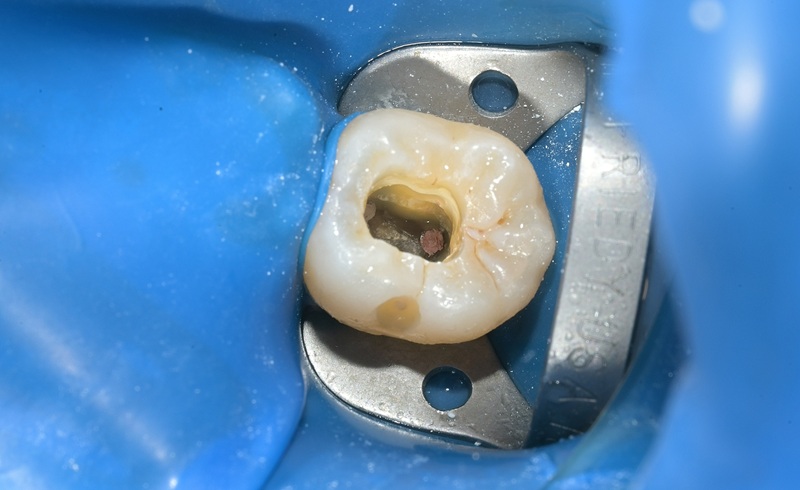

術前

術中

| 治療名 | セラミックインレーによる虫歯の再治療症例 |

|---|---|

| 治療説明 |

過去に治療された銀歯が外れたとのことで来院されました。内部には古い接着剤の劣化と虫歯の再発が見られたため、しっかりと虫歯を除去し、セラミック製の詰め物(インレー)で再修復を行いました。 セラミックインレーは、天然歯に近い色調と自然な透明感を持っており、見た目が気になる部位にも適しています。 |

| 治療回数・期間 | 2回 |

| 副作用とリスク | ・保険診療の銀歯に比べて費用が高くなります。 ・治療直後は一時的に知覚過敏のような症状が出ることがありますが、ほとんどの場合は数日〜1週間程度で落ち着きます。 |

| 料金(税込) | 77,000円 |